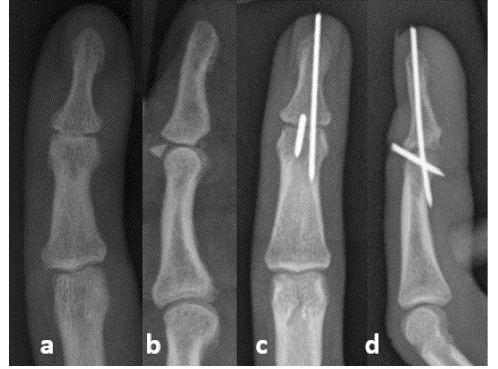

В данной статье представлен хирургический метод закрытой фиксации с использованием блокирующих спиц К.

При нахождении дистального межфалангового сустава в положении сгибания в дистальную головку средней фаланги вводят спицу Киршнера диаметром 1,0 мм и слегка переразгибают дистальную фалангу для прикрепления костного фрагмента к основанию фаланги. Имплантированные спицы К служат опорой для костных фрагментов. Затем просверлите вторую спицу К через дистальный межфаланговый сустав для фиксации.

Через 6 недель имплантат удаляют и проводят реабилитационные упражнения.